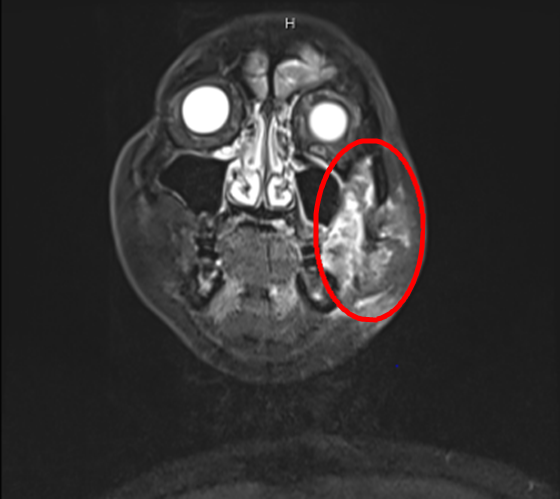

近日,湘雅常德医院口腔外科为一例口腔颌面肿瘤患者成功实施颊颌颈及侧颅底根治术,切除了颊部肿瘤及面部肌肉皮肤组织、口底组织、一侧下颌骨、一侧部分上颌骨及颈部淋巴结组织...